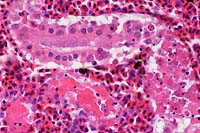

- Case 8-2. Otic vesicle, Brain. The otic vesicle is

heavily infiltrated by inflammatory cells and fibrin, and contains

a mineralized otolith. The connective tissue between the brain

and otic vesicle is similarly infitrated by abundant inflammatory

cells.

Brown

& Brehn, 40x obj

- Case 8-2 . Skull. Some macrophages in the exudate

surrounding the otic vesicle contain abundant Gram positive cocci.

20x

obj

- Case 8-2.Gill filaments and lamella. The interlamellar

space is partially filled between most gill lamella by an infiltrate

of macrophages, lymphocytes, and fewer mucus cells and/or epithelial